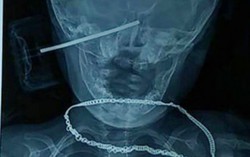

Té ngã, bé gái 11 tháng bị đồ chơi sắc nhọn cắm vào đầu

Phòng & chữa bệnh 15:18 06/07/2017Không may bị ngã khi đang cầm bánh xe ô tô đồ chơi, bé gái 11 tháng tuổi bị đồ chơi sắc nhọn cắm sâu vào đầu.